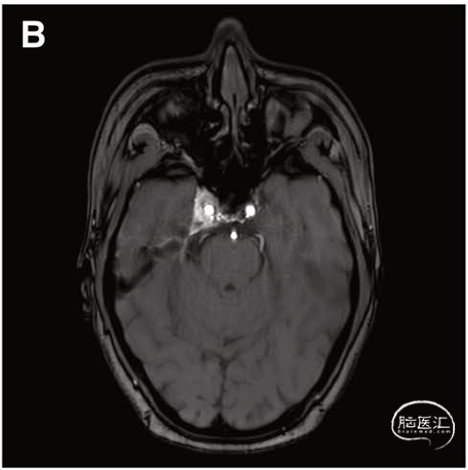

本研究报道了一例27岁女性海绵窦区硬脑膜动静脉瘘(CS-DAVF,Barrow D型)患者的诊疗经过。该患者因轻微头部外伤后出现右侧搏动性突眼及搏动性耳鸣,此前在外院曾尝试两次常规血管内栓塞治疗,均因无法开通岩下窦、面静脉等通路而失败。患者随后转诊至华山医院,经数字减影血管造影(DSA)检查明确诊断:病变血供主要来源于右侧颈内动脉脑膜垂体干、右侧咽升动脉以及左侧颈内动脉脑膜垂体干,静脉引流则以眼下静脉为主。

血管内栓塞本是治疗该类疾病的首选方法,但约10-20%的患者,会因先天发育异常、既往炎症或血栓形成,导致岩下窦或眼上静脉等自然通路完全闭塞,致使常规介入手术无法实施。面对这一临床困境,华山神外团队提出了创新思路:借助神经外科成熟的内镜经鼻蝶手术经验,建立一条全新的直接穿刺通道。